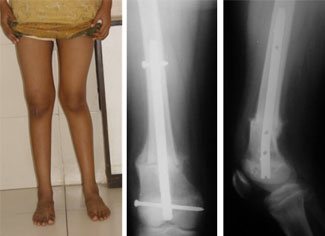

These are pictures taken about 10 weeks post surgery. She is able to bear full weight on the leg. The clinical appearance of the operated left side as seen in the picture on the left. The un-operated leg on the right side can be compared with the left side.

The pictures in the center and right show the x-rays with good amount of callus formation and strong healing. The osteotomy line is still seen, which disappears in another 6-8 weeks.

The final result after correction of both sides with excellent functional results. She has full flexion at the knee, able to sit cross-legged and able to perform all activities comfortably.